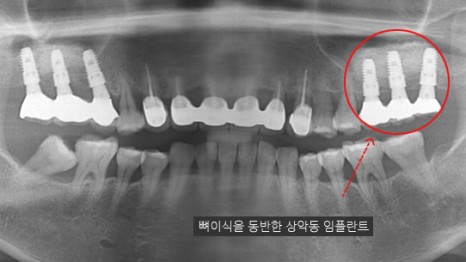

치아를 상실한 후 시간이 오래 지나

치조골 상태가 약화된 경우,

뼈이식이 필요할 수 있으며,

상황에 따라 상악동 거상술이 요구될 수도 있습니다.

또한, 구강악안면외과 전공과 방대한 임상 경험을

기반으로 고난이도의 뼈이식술과 광범위한 치료를

안정적이고 효과적으로 제공하고 있습니다.